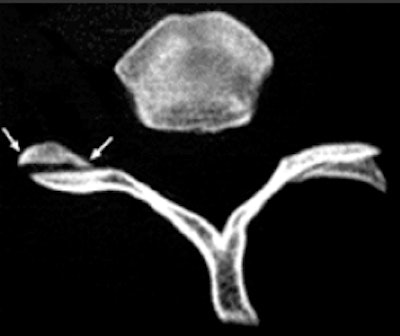

On CT, the vertebral facet joint space can look like a hamburger. All images courtesy of Fathima Hasan Mohamed.Hamburger: "My own personal favorite," Mohamed commented. On axial CT, the vertebral facet (apophyseal) joint space can look like a hamburger. When the facet joint is dislocated, the articular facets become uncovered, or naked, and this is also called naked facet sign. This CT sign is characteristic of a flexion-distraction injury and indicates severe ligamentous disruption and spinal instability. It may be unilateral or bilateral, depending on the facet dislocation.